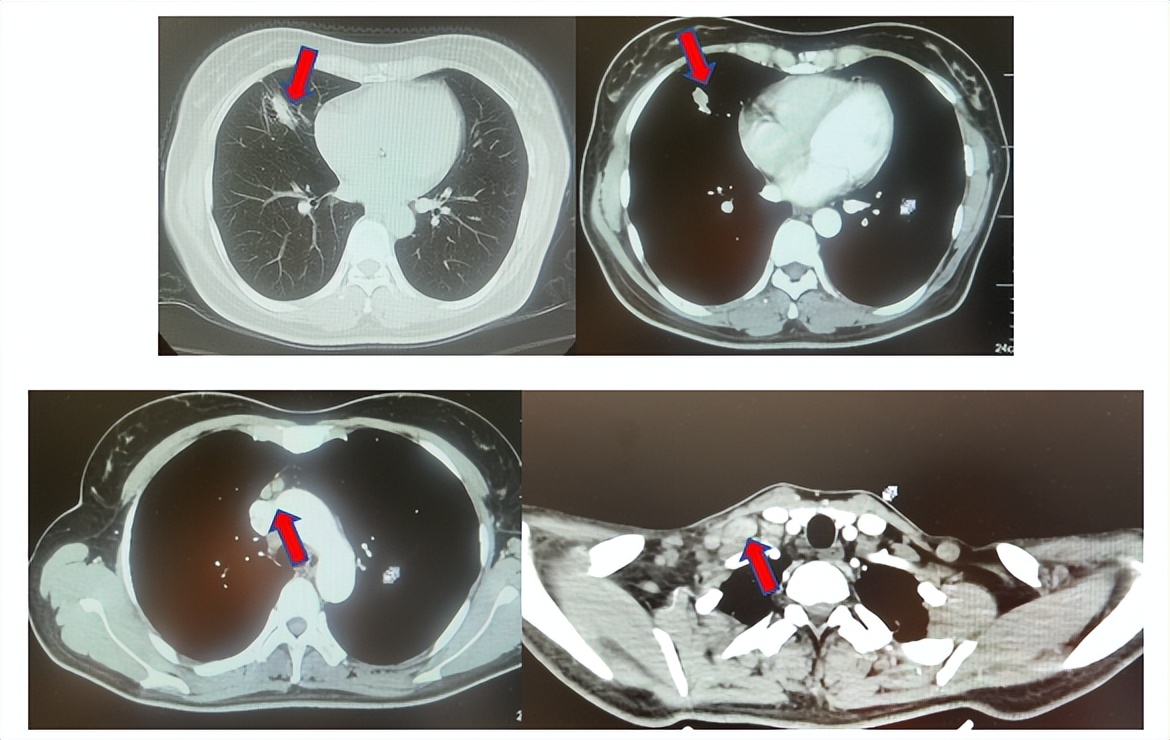

2.2影像学检查(图5)

肺+全腹CT增强:右肺中叶肿块,考虑恶性,双肺胸膜下炎症,双侧胸膜局限性增厚,右侧锁骨上淋巴结增大,纵隔淋巴结稍大;

颈部CT增强:右侧锁骨上及右颈部、纵隔多发淋巴结肿大。

脑MRI增强:头MR平扫+增强未见确切异常。

骨ECT:正常骨相(定期复查)。

图5:上两图分别展示基线时肺CT肺窗及纵隔窗右肺中叶病灶影像,下两图表示基线状态时纵隔淋巴结及锁骨上淋巴结影像。